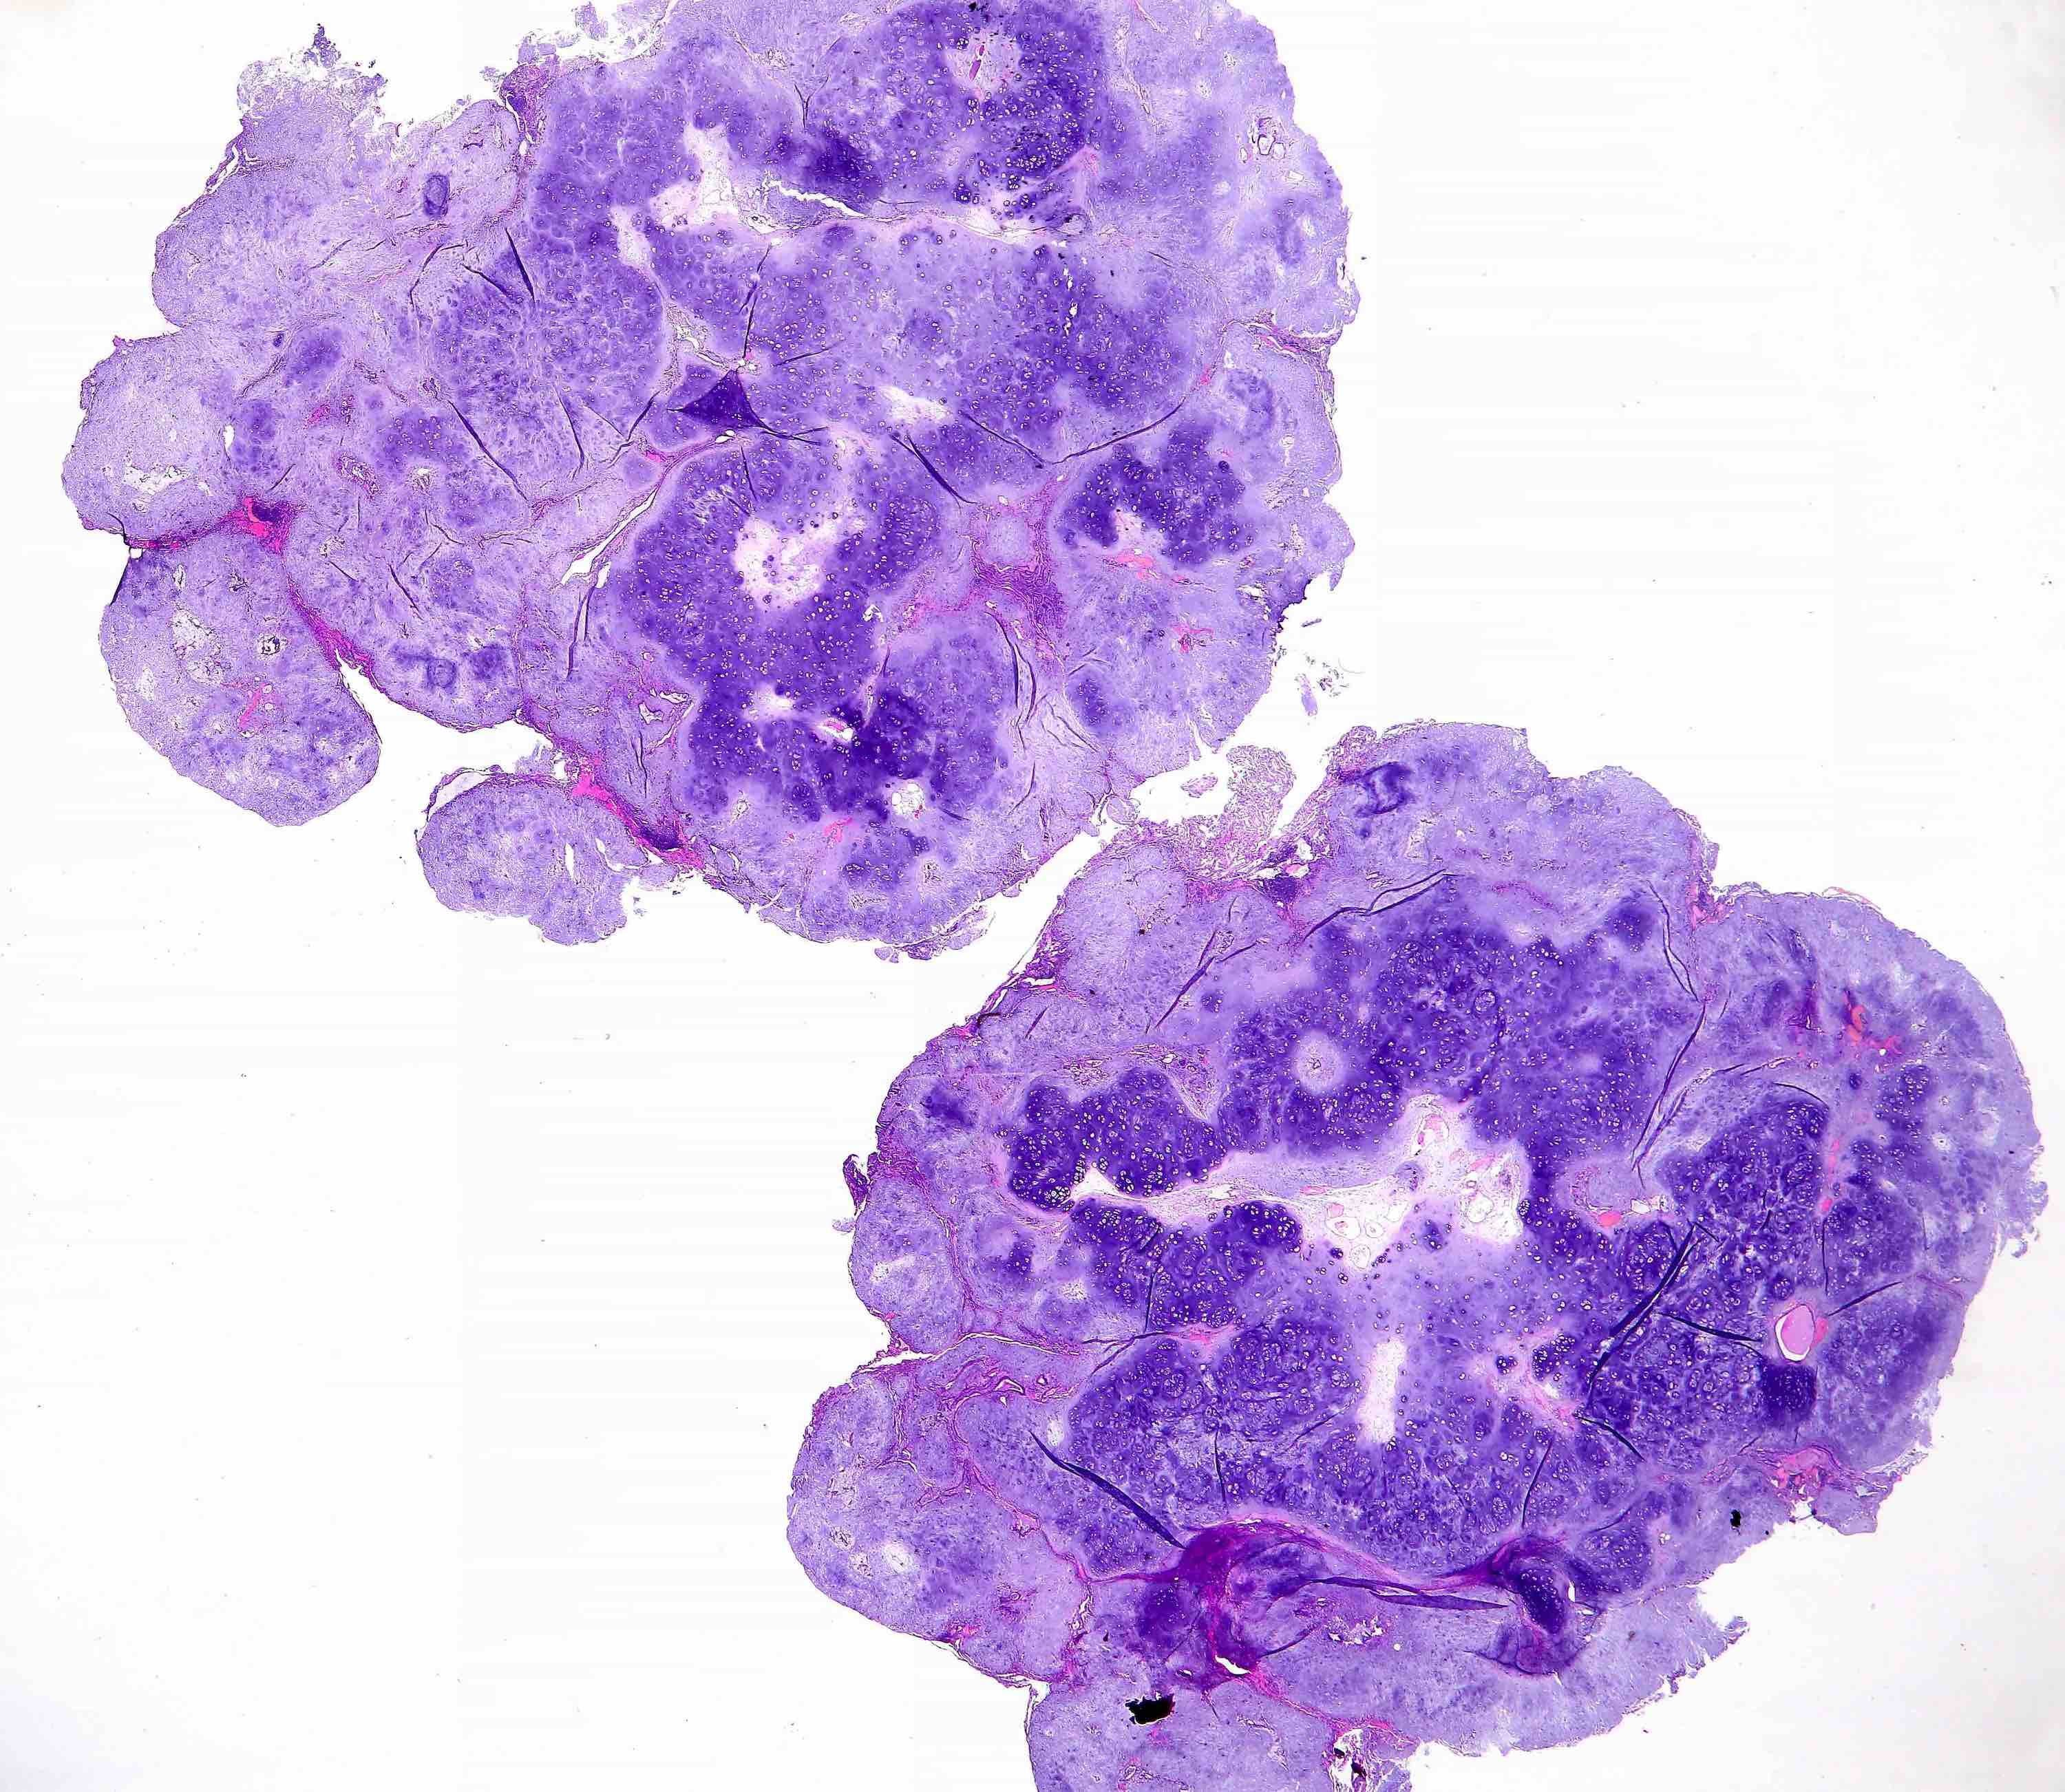

Microscopic (histologic) description

- Composed predominantly of varying degrees of mesenchymal tissue: hyaline cartilage, fat, smooth muscle and bone

- Other connective tissue elements may be present, represented by bland spindle cells, fibrous tissue or myxoid change

- Variably conspicuous, entrapped benign epithelial cells

- Reference: Thorax 1987;42:790

Microscopic (histologic) images

Contributed by Hui-Hua Li, M.D., Ph.D. and Jefree J. Schulte, M.D.

Contributed by @Andrew_Fltv on Twitter